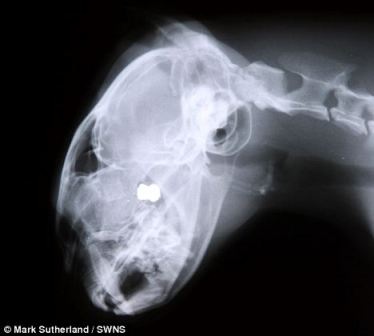

Sau khi tiến hành chụp X-Quang, các bác sĩ thú y đã phát hiện thấy một viên đạn nằm sâu bên trong não của Cookie. Các bác sĩ cũng cho biết, trường hợp này không thể phẫu thuật để lấy viên đạn ra được, nếu tiến hành phẫu thuật thì nguy cơ Cookie chết là rất cao.